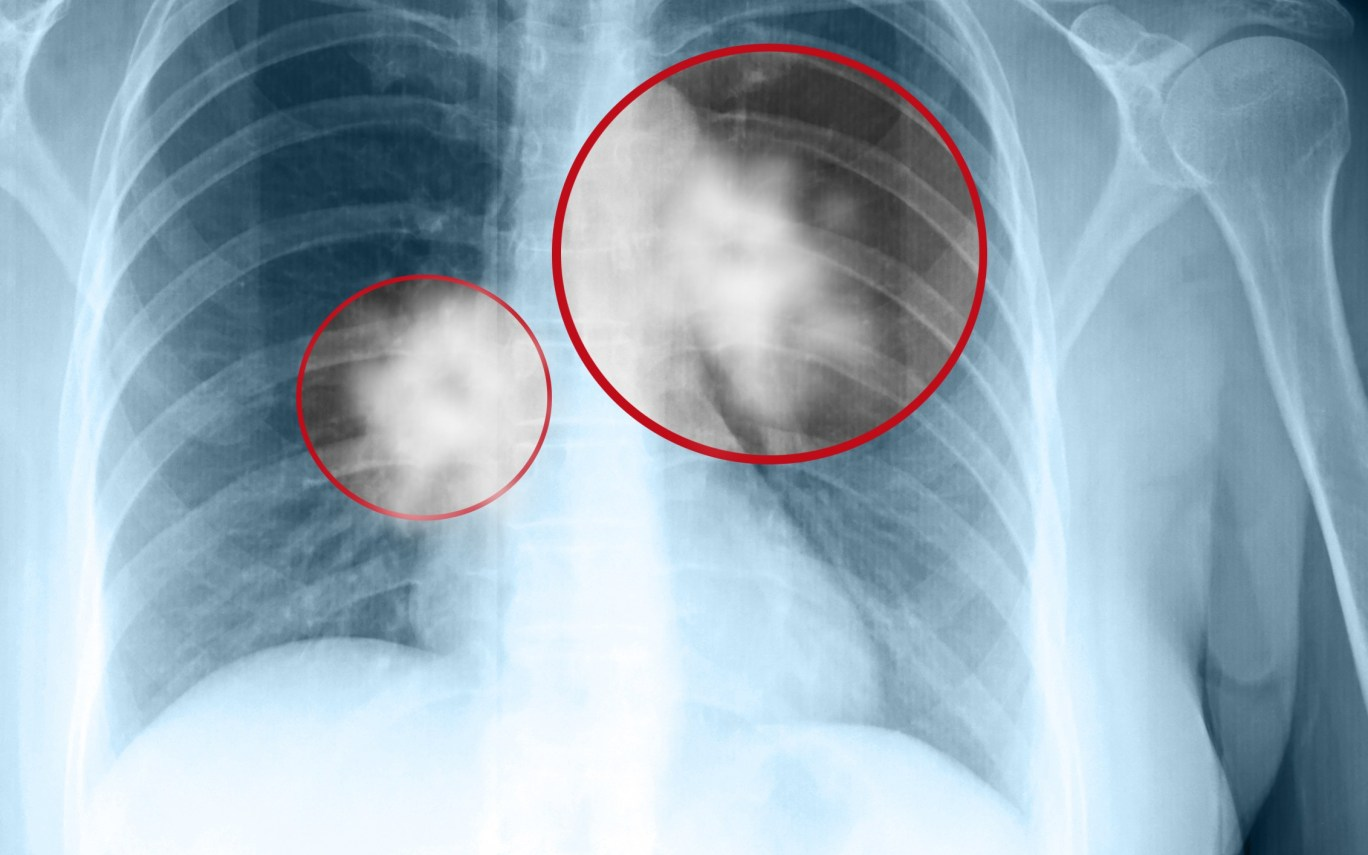

Ho kéo dài hơn 3 tuần đã không còn là chuyện “cảm cúm”. Nó là một dấu hiệu bắt buộc phải kiểm tra cho ra ngô ra khoai. Tôi bảo ông chụp phim. Khi hình ảnh hiện lên trên màn hình, người con trai đứng cạnh khựng lại. Người vợ nắm chặt tay chồng. Còn tôi… im lặng vài giây trước khi nói. Không phải vì tôi chưa từng thấy ung thư phổi. Mà vì trong hồ sơ cũ của ông, cách đây chưa đầy một năm, chỉ có một dòng rất quen thuộc:

Kết quả kiểm tra hôm đó không dễ nói ra: Tổn thương phổi ác tính. Khả năng đã tiến triển. Thể trạng suy giảm rõ. Khi tôi giải thích, ông ngồi im rất lâu. Bàn tay gầy đặt lên đùi, siết chặt. Người vợ khóc nấc, liên tục xin lỗi. Tôi buộc phải nói một sự thật đau lòng, nhưng cần phải nói:

“Ung thư phổi không đáng sợ bằng việc chúng ta bỏ qua nó vì nghĩ là viêm nhẹ. Bác không hại phổi bằng thuốc lá. Nhưng bác đã vô tình làm cơ thể suy yếu bằng cách ăn kiêng cực đoan, thiếu đạm, thiếu năng lượng – trong khi khối u vẫn âm thầm lớn lên.”